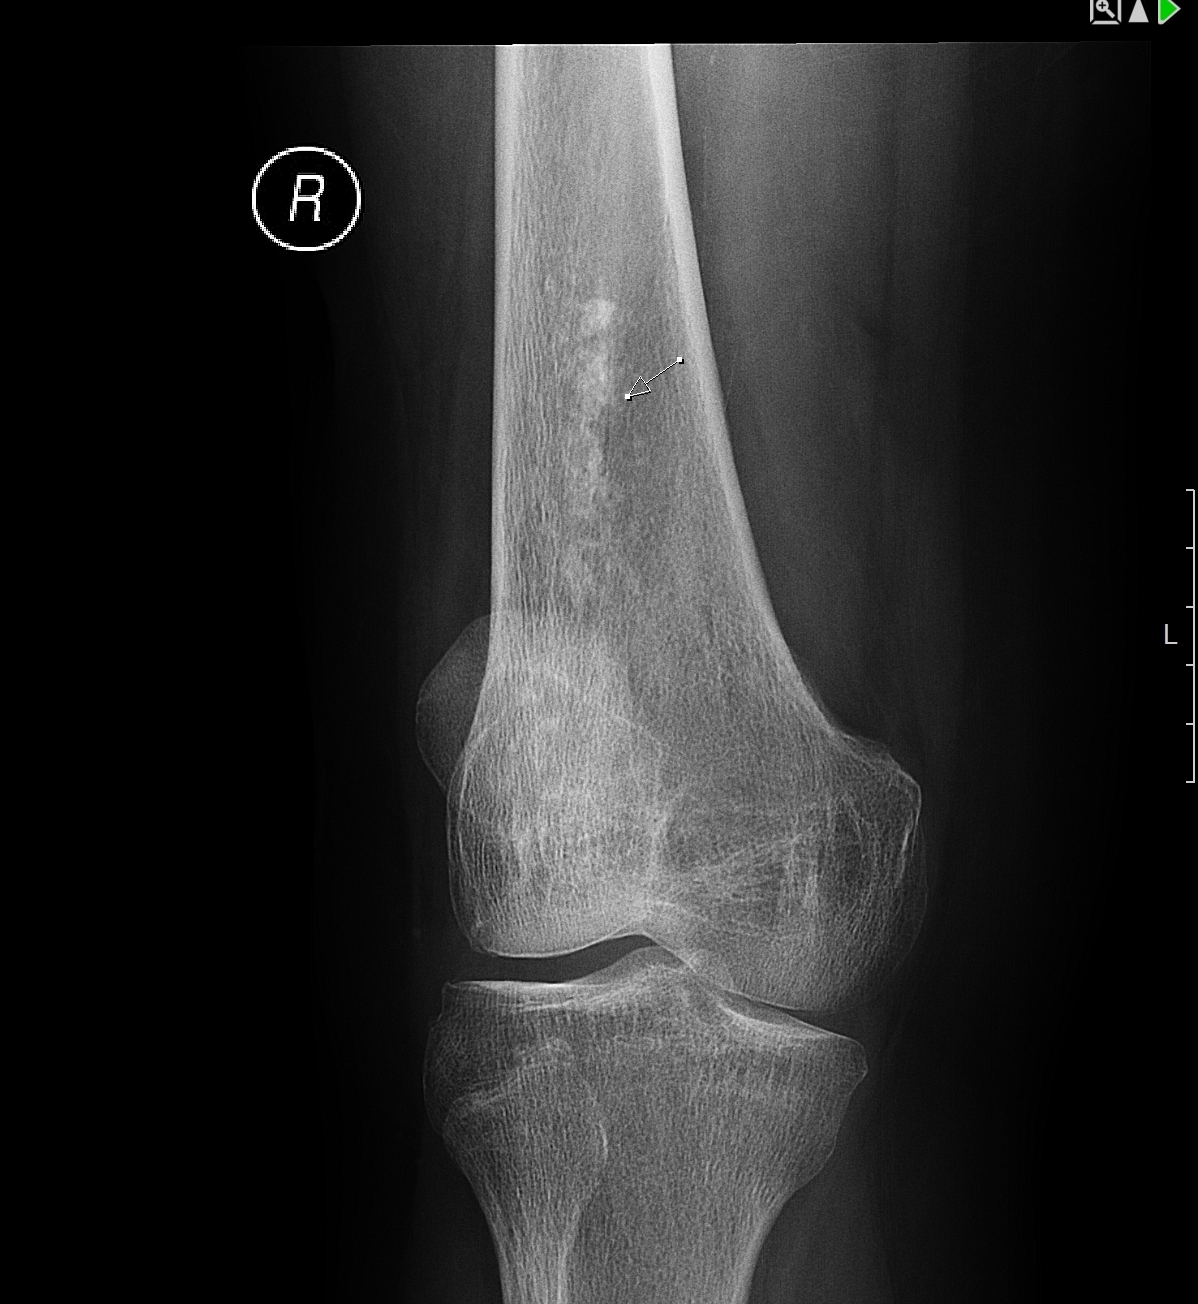

Рентгеновские снимки остеосклероза костной ткани